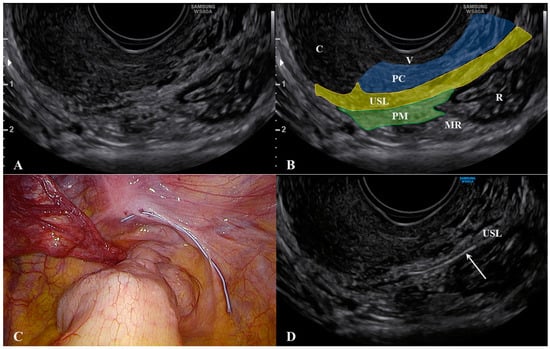

2.1. The Uterosacral Ligament

2.2. The Parametrium

2.3. The Paracervix

3. What Ultrasound Should Investigate and Detect

4. Anatomical Considerations and Surgical Implications

- Scioscia, M.; Virgilio, B.A.; Scardapane, A.; Pontrelli, G. Fusion Imaging: A Novel Diagnostic Tool for Nerve-Sparing Surgery for Deep Infiltrating Endometriosis. J. Minim. Invasive Gynecol. 2020, 27, 246–247. [Google Scholar] [CrossRef]